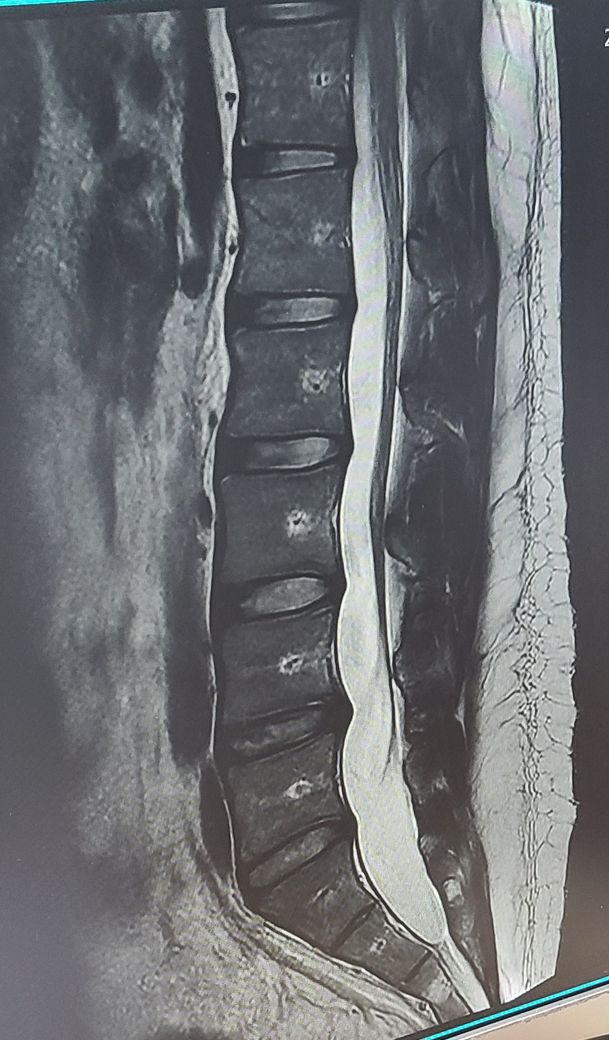

올려주신 mri 사진을 보면 요추 4~5번 디스크 부위가 약간 돌출 또는 수핵 탈출 가능성도 보이고 디스크 간격이 좁아져 있는 느낌도 있습니다.

요추 4-5번 간 디스크, 5번 요추-천추간 디스크 상태가 좋지 않습니다. 망가진 디스크는 완전히 회복시킬 수 없으므로 더 진행하지 않게 잘 관리하며 지내셔야 합니다. 통증이 한 번 나타나면 2-3개월은 지속되는 편이고, 통증이 사라지더라도 과체중, 부적절한 자세와 같은 원인이 사라지지 않으면 지속적으로 재발하여 통증을 유발할 수 있습니다. 심지어는 디스크 탈출증이 더 심해지고 진행하여 통증이 악화될 여지도 있습니다. 그러므로 지금 당장 시행해야 하는 것은 체중감량이라 보입니다.